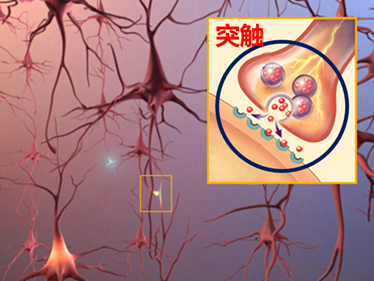

发病机制[3]成年人大约有一千亿个神经细胞(神经元),细胞之间的分支有超过一千兆个连结点,而神经元正是阿兹海默症破坏的主要对象。

两神经细胞间倚靠突触释放神经传递物质,藉以传递信号。但突触除释放神经传递物质外,也会释放一种有害的β淀粉样蛋白的小肽。在代谢正常的情况下,此蛋白能被清理掉,但若释放过多β淀粉样蛋白或来不及清理,就会凝结成一起形成蛋白质小块进而累积成斑块。

形成的蛋白质小块会刺激免疫细胞导致发炎并吞食已丧失功能的细胞,使得突触被破坏。此外,Tau蛋白的过度磷酸化也会形成扭曲的神经纤维缠结,从内部阻塞神经元致使营养物质无法传送,最后使得细胞凋亡。